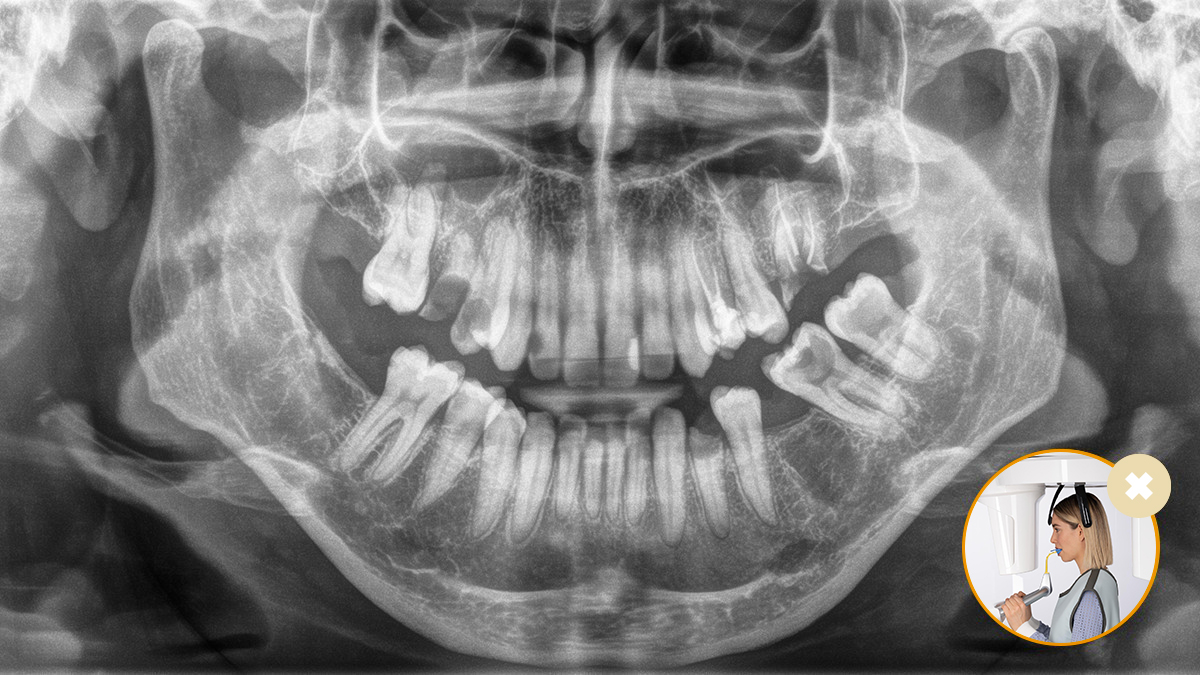

El posicionamiento correcto del paciente permite obtener imágenes de alta calidad que respaldan un diagnóstico preciso y facilitan y mejoran la experiencia del paciente.

Este es nuestro concepto de 10 puntos para facilitar el posicionamiento del paciente y la obtención de imágenes radiológicas. Se trata principalmente de dos cosas: alta calidad de imagen y comodidad para el paciente y el asistente.

Imágenes de cómo trabajar con nuestro concepto de posicionamiento de pacientes y asistente de imágenes

El resultado: Escaneos precisos gracias al bloque de mordida oclusal